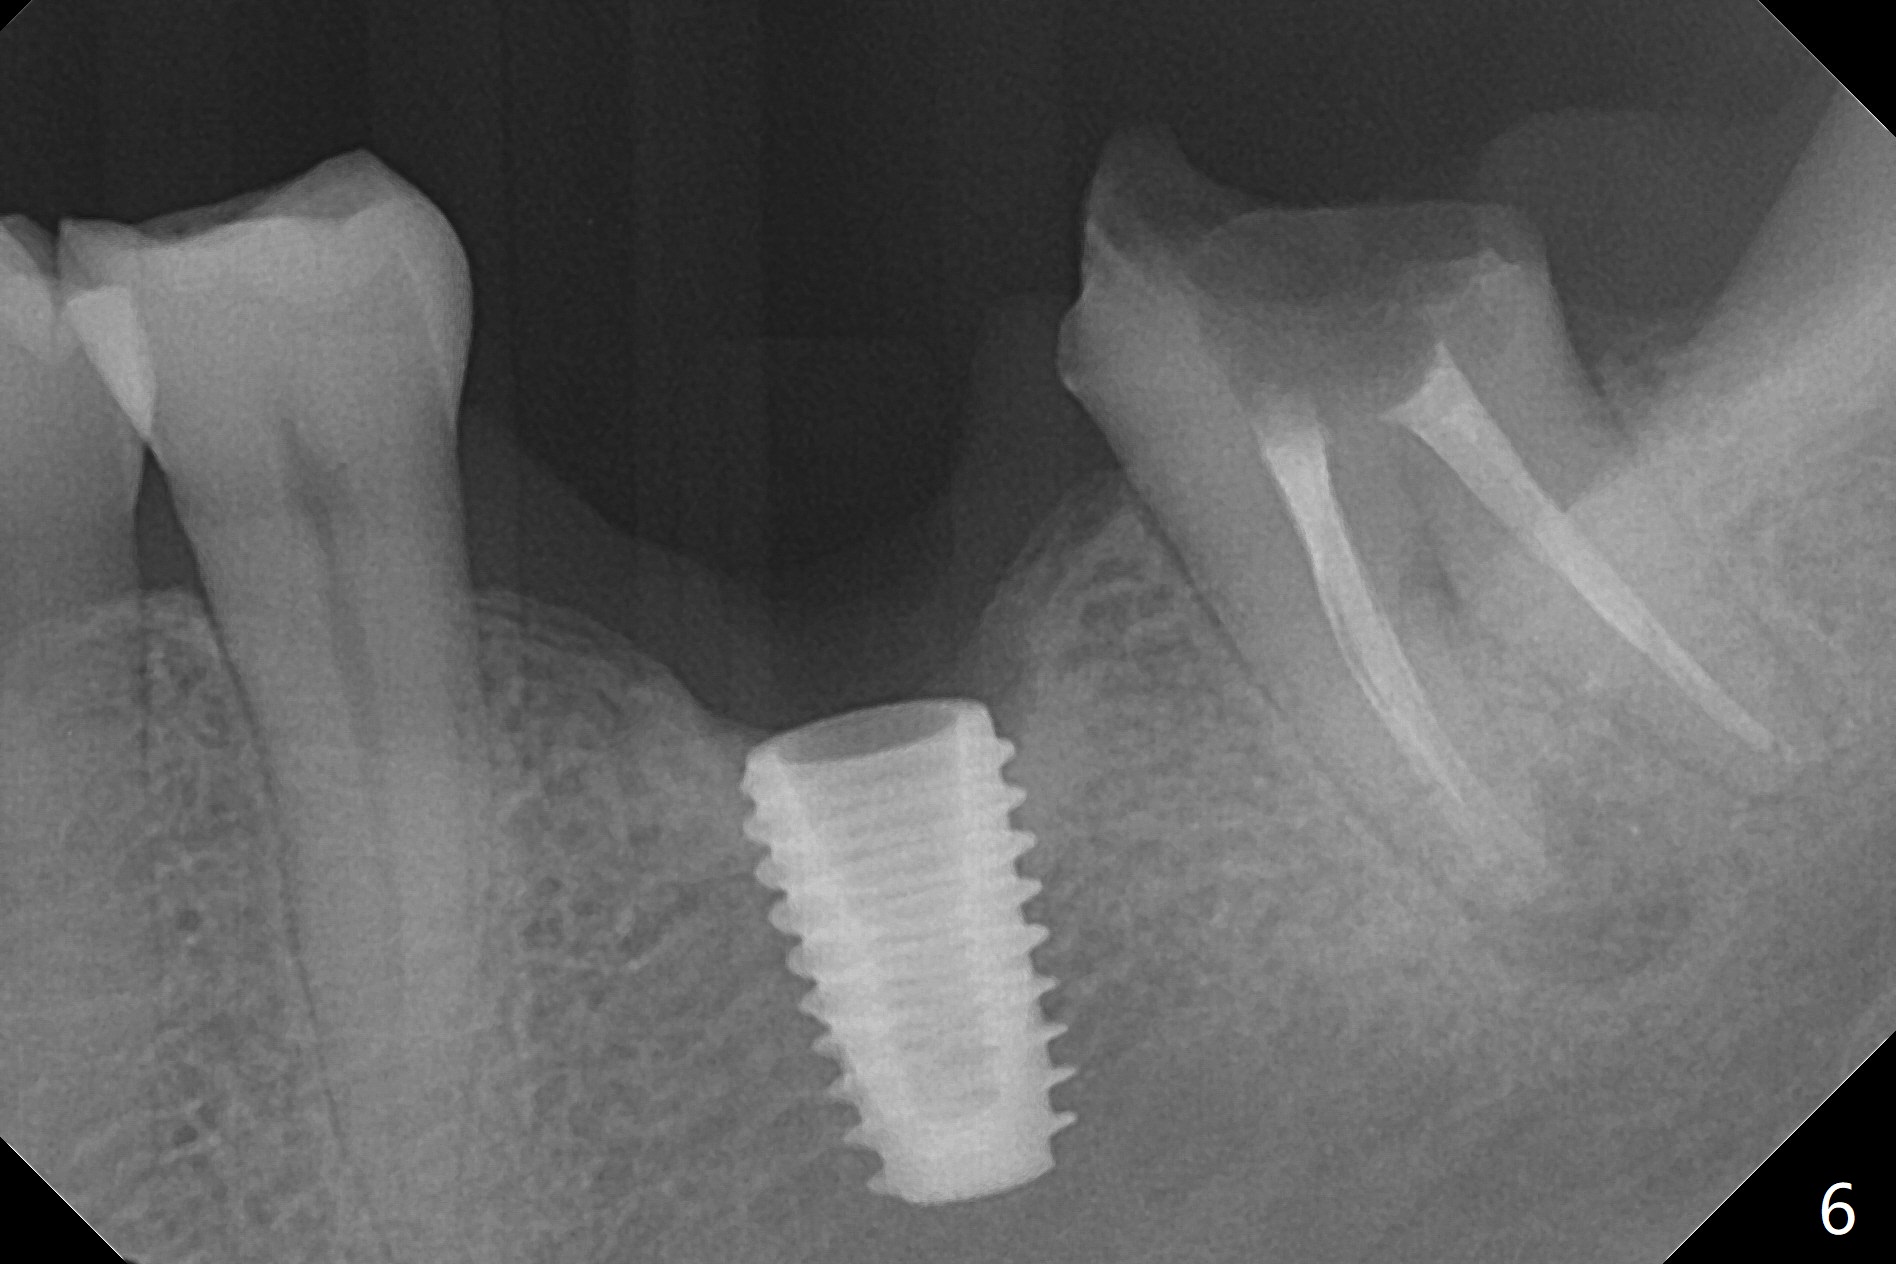

With one carpule of Xylocaine (34 mg with 17 mcg of Epinephrine), a 5x8.5 mm implant is placed at #19 in a timely and painless manner. The patient is pleased as compared to her previous implant placement at #3 and 30. Due to the thin buccal bone, the implant is placed ~.5 mm deeper than designed; a 6.5x4(2) mm healing abutment is incompletely seated (Fig.1). A smaller and skinny one (5.5x7(4) mm) is seated normally (Fig.2). Regional panoramic X-ray shows clearance from the Inferior Alveolar Canal (Fig.3 *). Although there is crestal bone resorption 6 months postop, the bone density next to the 1st thread is high (Fig.4 >). A 5.5x4(4) mm cemented abutment is placed for impression. The patient returns with #18 crown dislodgement and #19 crown loosening 11 months post cementation (Fig.5 <: gap between implant and abutment). Since the crown and abutment are unable to be torqued properly, they are removed (Fig.6). A narrower abutment is able to be seated apparently completely while a metal post (Fig.7 *) is tried in in the distal root of #18. To reduce the chance of re-fracture of #18 crown, the tooth #15 needs to be distalized orthodontically so that an implant will be placed at #14 (Fig.5).